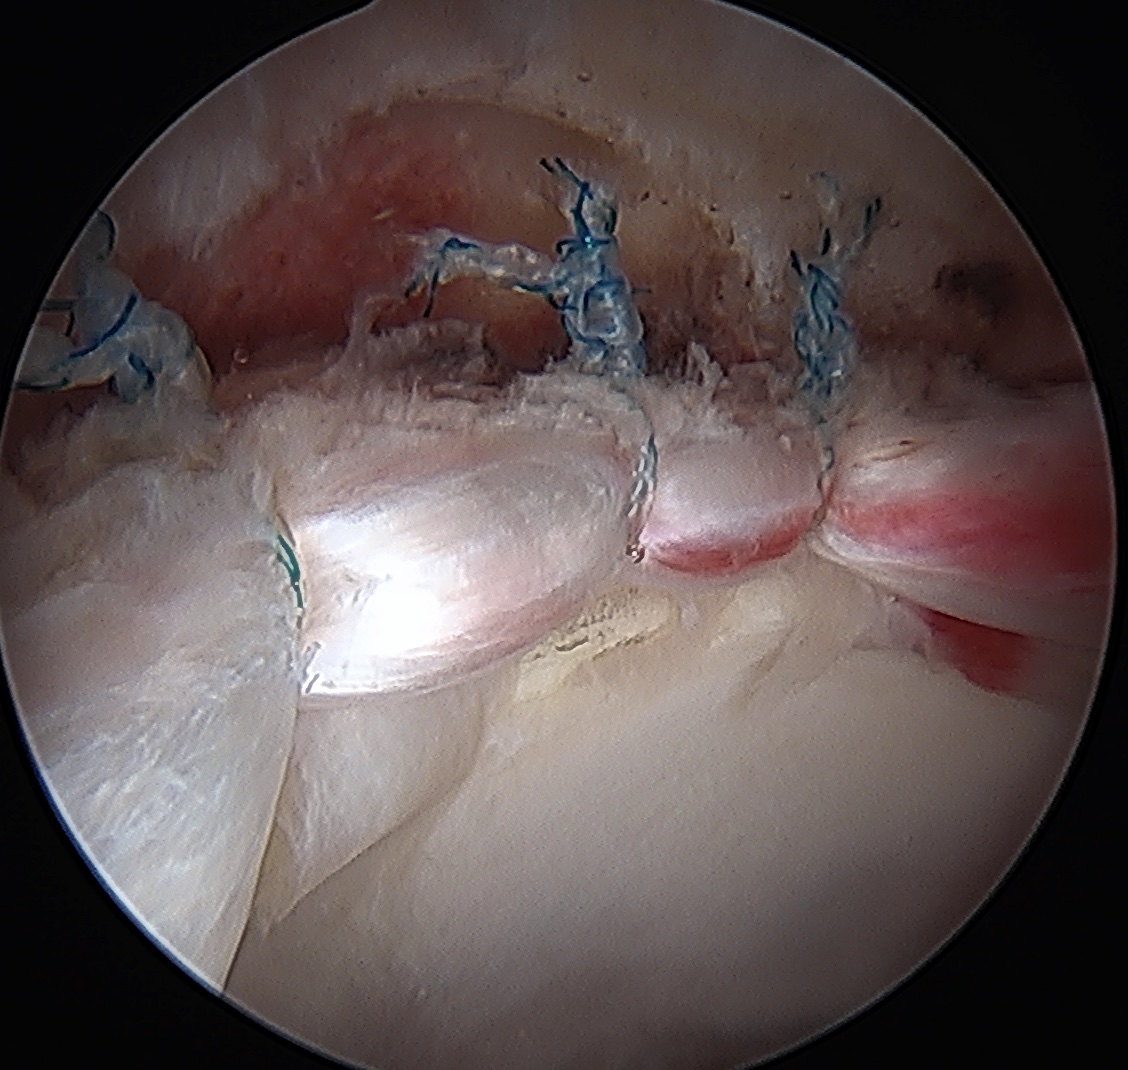

Capsular Repair

T capsule closure

Interportal capsule closure

Capsular retear / deficiency

- may cause microinstability / pain

- most studies point towards superior outcomes with capsular repair